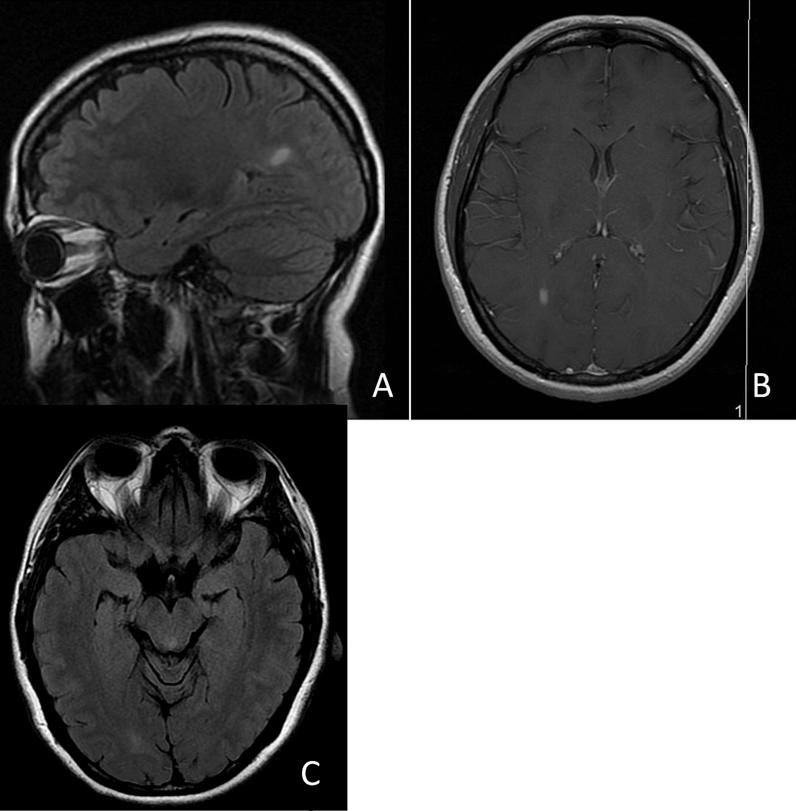

Ten patients were included who had developed initial MS symptoms after COVID-19 infection. Gender distribution was equal (50% male). The mean age was 28 (range 17-39) years. Average time to neurological presentation was between 2 and 6 weeks following acute COVID-19 infection. Partial transverse myelitis was the initial presentation in 40% of the cases, and 60% of patients had spinal cord lesions present at the moment of diagnosis. All patients showed enhancing lesions on brain magnetic resonance imaging (MRI). The presence of cerebrospinal fluid (CSF) oligoclonal bands was found in all six tested cases. The majority of patients (80%) were unvaccinated for COVID-19. The two vaccinated patients had received two doses of the monovalent COVID-19 messenger ribonucleic acid (mRNA) (Pfizer Biotech) vaccine and no booster, a year prior to contracting COVID-19.

MS患者组结果:纳入了10例在COVID-19感染后出现初始MS症状的患者。性别分布均衡(男性占50%)。平均年龄为28岁(范围17 - 39岁)。急性COVID-19感染后至出现神经症状的平均时间为2至6周。40%的病例初始表现为部分横贯性脊髓炎,60%的患者在诊断时存在脊髓病变。所有患者的脑部磁共振成像(MRI)均显示强化病灶。在所有6例检测病例中均发现脑脊液(CSF)寡克隆带。大多数患者(80%)未接种COVID-19疫苗。两名接种疫苗的患者在感染COVID-19一年前接种了两剂单价COVID-19信使核糖核酸(mRNA)(辉瑞生物技术公司)疫苗,且未接种加强针。